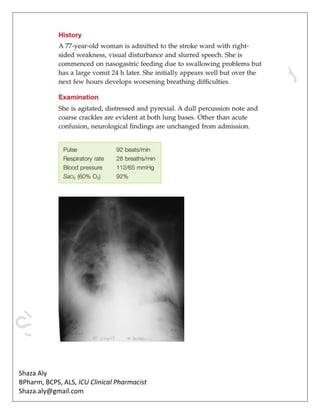

Type 1 Respiratory Impairment

• Type 1 respiratory impairment: low Pao2 with normal or low Paco2.

• The Paco2 is often low due to compensatory hyperventilation.

• If the arterial blood gas (ABG) is drawn from a patient on supplemental O2, the Pao2

•